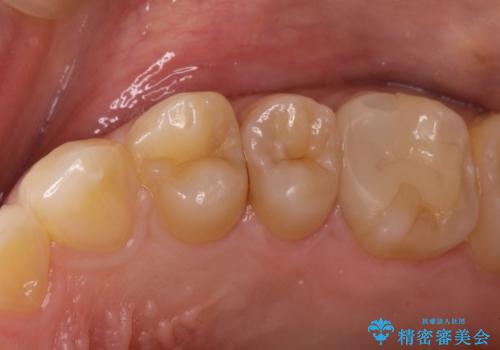

精密なむし歯の治療 セラミックインレー

- 定期健診にてむし歯を認めた患者さまです。

笑った時に見える部分だったためセラミックインレーにて修復しました。

保険治療で使える材料には制限があり、見た目だけでなく精度でも劣ります。当院でのセラミックインレーは歯とのつなぎ目を拡大鏡で確認して精度高く仕上げるため、むし歯のリスクを限りなく少なくできるよう治療します。